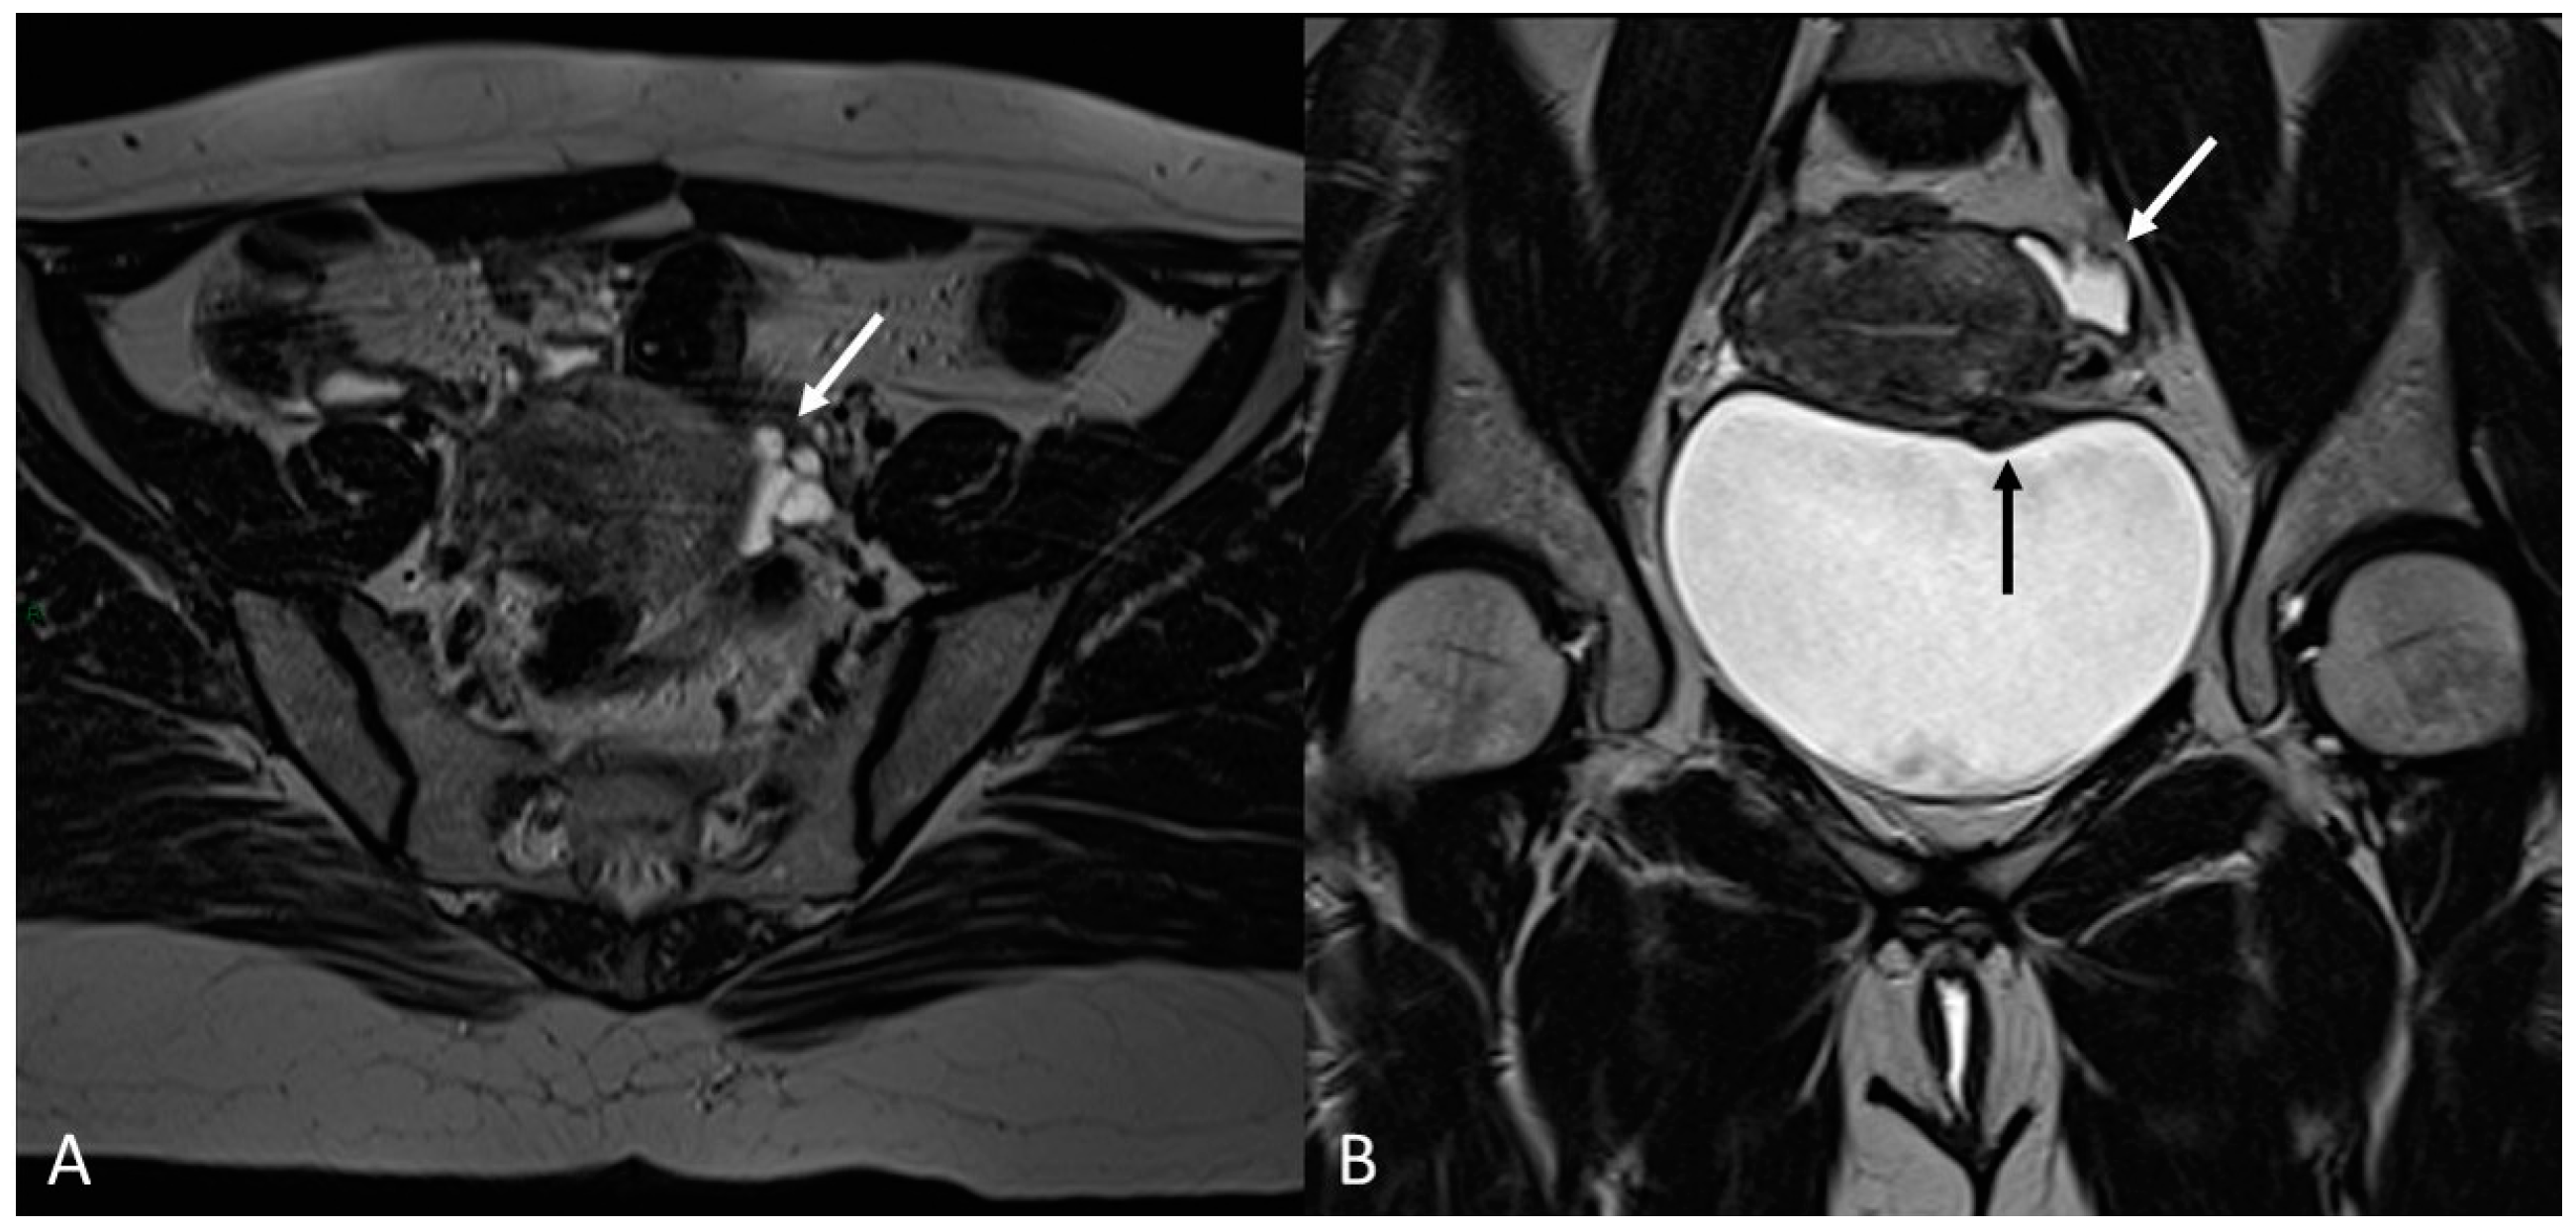

In order to perform a correct evaluation, the bladder must be at a degree of repletion suitable for the correct study of its walls and its lumen: those nodules or masses are responsible for the loss of the normal hypointense signal of the muscularis layer on T2WI. Hemorrhagic content may also be seen as hyperintense foci on T1WI, and it is also possible to observe hyperintense cystic areas on T2WI [7,14] (Figure 1).

Figure 1.

Localization of endometriosis in the vesico-uterine pouch in a 42-year-old female. (A) Sagittal T2WI (black arrow); (B) Sagittal fat-suppressed T1WI (white arrow); (C) Coronal T2WI (black arrow).

In the case of a mural mass protruding into the lumen, mucosal or submucosal edema is well depicted on T2WI [40].